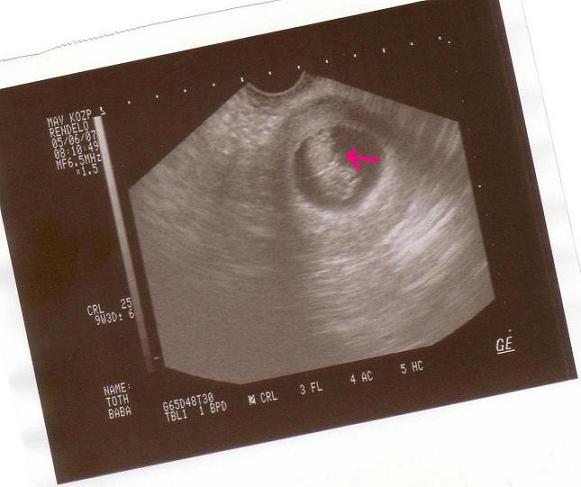

Voltam uhun reggel, 25 mm a baba 9+3 idős, szóval ritka tökéletes ciklusom lehetett, amikor megfogant.....és és és láttam a kezét, ahogy kalimpál, meg amikor szétterpesztette a lábát!!!!!!!!!!!!Megható volt.

Este rakok képet..............